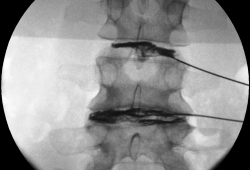

In de behandelzaal neemt de patiënt plaats op de behandeltafel in buikligging. Er wordt een pijnstillend en een licht kalmerend middel toegediend. Het aanprikken gebeurt met behulp van röntgendoorlichting. Eens de plaatsbepaling gebeurd is wordt de rug ontsmet om infectierisico te beperken. De huid wordt lokaal verdoofd. Dit kan branderig aanvoelen. Een naald wordt ingebracht tot in de discus. Daarna wordt een contrastmiddel ingespoten. Zowel de eventuele pijn die de patiënt hierbij ervaart als de structuur van de discus wordt hierbij geëvalueerd.